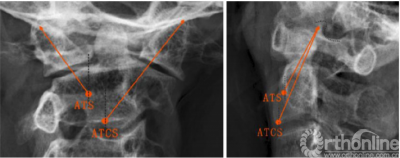

ATS和ATCS固定的轨迹可通过正、侧位X线片上的解剖标志来确定。在正位X线片中,螺钉轨迹朝向C1上关节突上外侧角,与侧块外侧缘间隙为2-3mm(图3,左)。然后测量α角,即ATS与ATSC螺钉相对于矢状面所形成的理想外展角。在侧位X线片中,ATS和ATCS固定方向均朝向C1上关节突后上角,并与上关节突后缘的间隙为2.3mm(图3,右)。此外,还测量了角β,即ATS与ATSC螺钉相对于冠状面所形成的理想倾斜角。将螺钉置入新鲜尸体标本后,在正、侧位X线片上分别测量ATS和ATCS的实际角α、β,以及ATCS和ATS的实际进钉点与C2椎体中线的横向距离。

图3正位和侧位x线片上ATS和ATCS的螺钉轨迹,(左)所有螺钉对准C1上关节突上外侧角;(右)所有螺钉对准C1上关节突上角(点附近);ATCS,前路经关节交叉螺钉;ATS,前路关节交叉螺钉

The ATS and ATCS trajectories were determined using the landmarks visible on anteroposterior and lateral x-rays. On the anteroposterior view, screw trajectories were aimed at the superolateral corner of C1 superior articular process, leaving 2–3 mm clearance from lateral margin of the lateral mass (Fig. 3, left). Then, the angle α, the ideal lateral angle of ATS and ATCS placement relative to the sagittal plane were measured. On the lateral view, the trajectories of ATS and ATCS were aimed at a point on the line between the superoposterior corner of C1 superior articular process and the superior end of the anterior arch, with 2–3 mm clearance from posterior margin of the superior articular process (Fig. 3, right). Moreover, the angle b, the ideal incline angle of the two screws placement relative to coronal plane were measured. After the screws were inserted into fresh cadaveric specimens, the actual angle a and b of ATS and ATCS were also measured on anteroposterior and lateral X-ray images, respectively, as well as the actual entry points of ATCS and ATS lateral from the midline of the C2 vertebrae.

Fig. 3 Trajectories of ATS and ATCS are shown on anteroposterior (left) and lateral radiographs (right). (left) All screws are aimed at the superolateral corner of C1 superior articular process (right) All screws are aimed at the superoposterior corner of C1 superior articular process (around dot). ATCS anterior transarticular crossing screw, ATS anterior transarticular screw